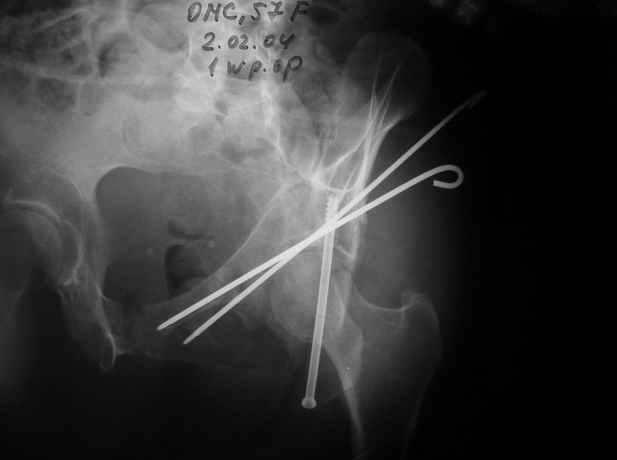

02.02.04